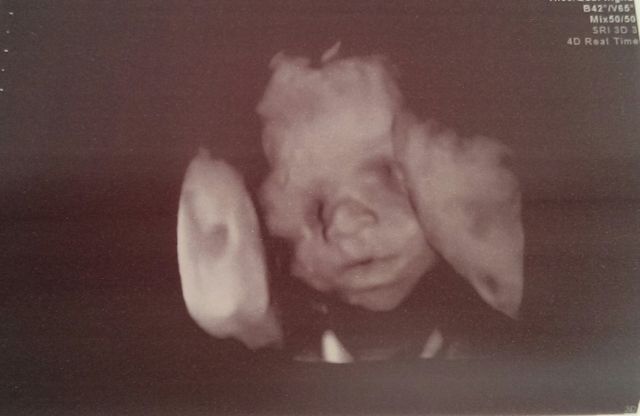

După mai multe săptămâni în care au stat cu sufletul la gură şi şi-au dorit să afle sexul bebeluşului, Ellie White şi logodnicul ei, Doru Tinca au primit vestea cea mare: vor avea o fetiţă. Instantaneu, artistei i-au dat lacrimile de fericire.

Însărcinată în 5 luni şi jumătate, cântăreaţa se gândea deja că dacă şi al doilea copil va fi tot băiat, va utiliza hăinuţele şi jucăriile lui Mihai. Nu va fi însă cazul. „«Este fetiţă!», mi-a spus doamna doctor în timp ce toţi ne uitam pe ecranul aparatului de ecografie. :) Ochii mi s-au umezit instantaneu! Deşi mă aflu la a doua sarcină, am fost compleşită de mari emoţii, aproape totul este diferit… toate trăirile sunt schimbate faţă de ceea ce am simţit la Mihăiţă“, a povestit Ellie White pe blogul ei. Vedeta le-a dat vestea fanilor, alegând să îşi facă astfel debutul în blogosferă.

După ce a aflat sexul bebeluşului, artista deja visează la hăinuţe roz şi păpuşi. Ellie White şi Doru Tinca au început să întocmească o listă cu posibile nume pentru micuţă. „Mai sunt aproape trei luni și jumătate pâna în momentul naşterii, însă bucuria de a avea o familie atât de frumoasă mă însoţeşte zi de zi. Un băieţel, o fetiţă și un viitor soţ care mă fac cu adevărat fericită!“, a adăugat artista.